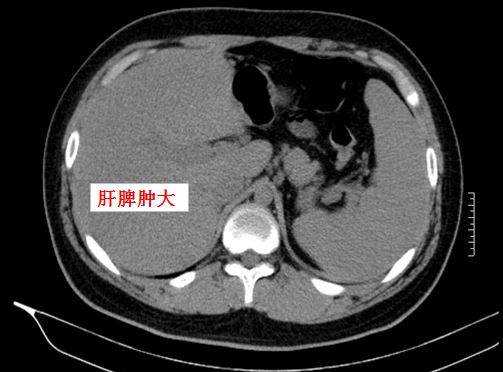

其中一類EB病毒感染為傳染性單核細胞增多癥,常見的臨床表現(xiàn)有發(fā)熱、咽峽炎、淺表淋巴結(jié)腫大(主要是雙側(cè)頸部)、皮疹(多見于軀干),可合并肝脾腫大、肝損傷、外周淋巴細胞及異型淋巴細胞增高(如下圖),多數(shù)預后良好,少數(shù)可出現(xiàn)嗜血綜合征。